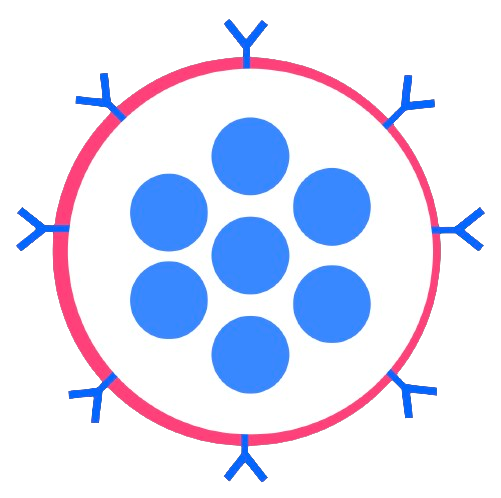

We will also perform the process of PEGylation, where polyethylene glycol (PEG) chains are conjugated (bonded) to a molecule. PEGylation of the nanogel surface imparts them with ‘stealth’ properties by making the surface more hydrophilic, shielding a charge that the core might carry, and establishing a physical barrier that reduces interactions with blood proteins. However, this is highly dependent on the size of the nanogel, its shape, molecular weight, and surface density of the PEG used. PEGylation is a process in which polyethylene glycol (PEG), a non-toxic and biocompatible polymer, is chemically attached to another molecule, such as a drug or a therapeutic protein. The main purpose of PEGylation is to improve the properties of the molecule it is attached to. This can include increasing the molecule’s stability, solubility, and duration in the body while also reducing immunogenicity (the likelihood of triggering an immune response). By doing so, PEGylation can enhance the efficacy and safety of medications, making them more effective for longer periods and reducing the frequency of dosing.

To cross the BBB, our nanogel will first be attached to red blood cells (RBCs) ex vivo and will then use red blood cells to get to the brain in a process known as red blood cell hitchhiking. We choose to attach the nanogel as opposed to loading it inside the RBCs as the nanogel can be released more easily and precisely, making this approach effective and efficient for drug delivery.

RBCs are abundant, readily available, and relatively expendable. They are simpler and more uniform than other cells, with each cell being about 6–7 micrometers wide and 2 micrometers thick. RBCs are shaped like biconcave disks, which allows them to have a larger surface area and flexibility, allowing them to carry more drugs and have a long-lasting presence in the bloodstream without being detected and eliminated by the immune system. Their incredible durability and flexibility come from their strong, elastic membrane and cytoskeleton, and their lack of nuclei and other internal structures. Not having a nucleus is important, as it provides RBCs with extra room to carry drugs and makes them suitable for genetic modifications. Furthermore, RBCs’ high flexibility allows them to move through very narrow blood vessels, such as those in the spleen and potentially the BBB. Furthermore, since RBCs travel within blood vessels, they minimize the interaction of the encapsulated drugs with other substances, lowering the chance of metabolic breakdown and reducing unintended side effects. Finally, RBCs have proteins on their surface that prevent them from being easily swallowed up by the immune system, allowing them to circulate for long periods and release drugs gradually.